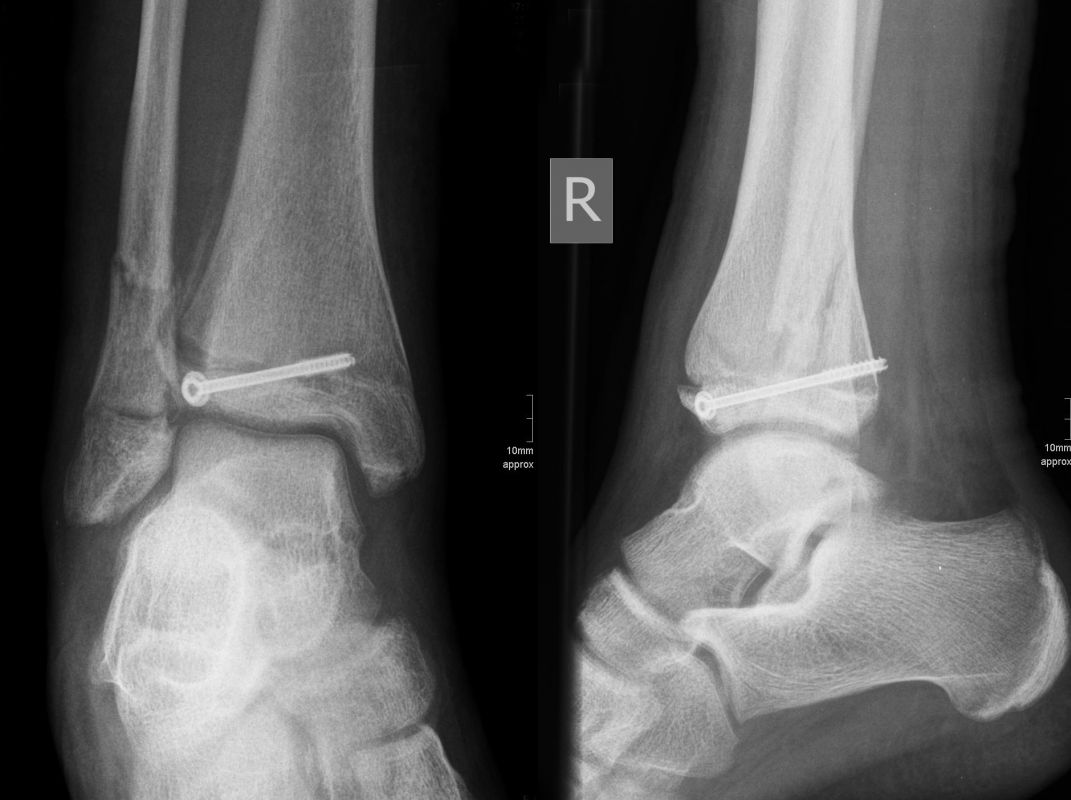

Dislozierte Frakturen (Frakturspalt > 2 mm) werden grundsätzlich operativ behandelt. Die Reposition kann arthroskopisch unterstützt erfolgen. Die Schraubenosteosynthese erfolgt entsprechend dem Frakturverlauf. Bei Twoplain Frakturen ist meist eine epiphysäre Schraube ausreichend die von lateral kommend das Fragment nach medial-proximal fixiert. Der Schraubenverlauf ist üblicherweise von lateral ventral nach proximal dorsal medial (Abb. 24). Nach Reposition darf in der seitlichen Aufnahme des Sprunggelenks, als auch in der 45° Außenrotationsaufnahme keine Stufe in Höhe der Wachstumsfuge erkennbar sein. Eine sichtbare Stufe ist Indikator für eine unzureichende Reposition.

Die Nachbehandlung umfasst eine sechswöchige Entlastung im Gips. Nach Gipsabnahme wird die Bewegung freigegeben und eine schmerzadaptierte Aufbelastung erlaubt. Ein Sportbeginn ist normalerweise nach 10-12 Wochen möglich. Die Schraubenentfernung erfolgt nach 3-6 Monaten. Klinische Kontrollen nach sechs und zwölf Monaten erlauben ein frühzeitiges Erkennen von möglichen postoperativen Fehlentwicklungen. Sobald die Wachstumsfuge vollständig verschlossen ist, sind keine weiteren Kontrollen mehr notwendig.